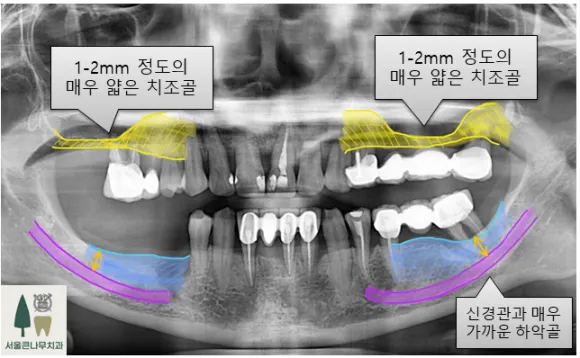

치료전 파노라마 엑스레이 사진

위의 치아의 경우 상악동이라는 공기주머니 구조물이 있어 상악동을 들어 올려 뼈를 보강해 주는 상악동 거상술 골이식 수술을 같이 병행하게 됩니다. 치료전에는 상악 치조골이 불과 1-2mm 밖에 없을 정도로 매우 얇은 상태였지만, 상악동 골이식술을 통해 골높이를 보상하여 임플란트를 식립하였습니다. 이러한 경우 대개 4-6개월 정도 소요되며, 기다리는 동안 환자분의 협조도가 매우 중요합니다.

아래 치아의 경우 임플란트를 식립하면서 치조골 이식술을 같이 병행하게 됩니다. 아래턱은 잇몸뼈가 약해지면 신경과의 거리가 가까워지는 경우가 많기 때문에 치아 발치 후 오래동안 방치되는 경우 임플란트 식립이 매우 힘들어지거나 신경 손상 우려가 있습니다.